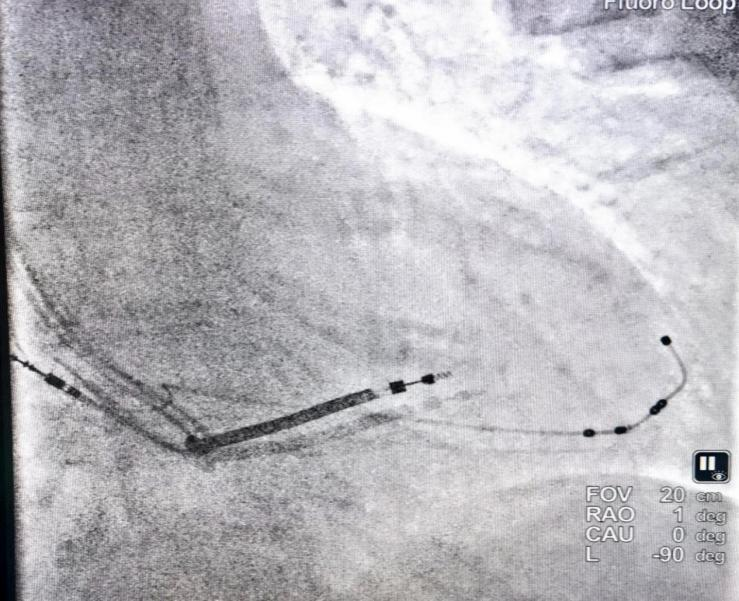

主动固定电极植入靶静脉后

同时,CRT-D植入术目前是起搏领域最复杂的术式之一,主要难点在于左室电极的植入,需要选择最延迟部位靶静脉植入左室电极,但是靶静脉选择面临诸多难题,困扰临床的还是电极固定,以及术后电极的稳定性;4798主动固定左室四极导线,有别于传统的被动固定左室导线,主动固定,减少脱位风险,简化手术流程,同时可以避免心尖部起搏。

刘元庆介绍,左室主动固定四极导线室全新的设计,有别于传统的被动固定方式,能够更好的降低电极脱位风险,同时简化了植入流程,缩短手术时间,此款电极兼容1.5T/3.0T磁共振扫描,为患者提供更多的选择,相信未来会有更多的患者因此获益。